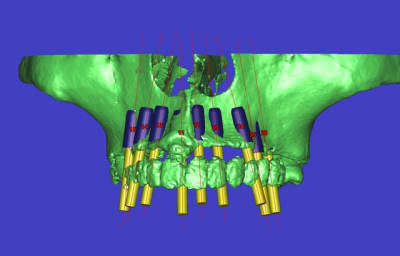

voilà, j'ai trouvé 5 mn...

le projet simplant est théorique, ça ne correspond pas à ce qui sera posé, c'était pour étude.